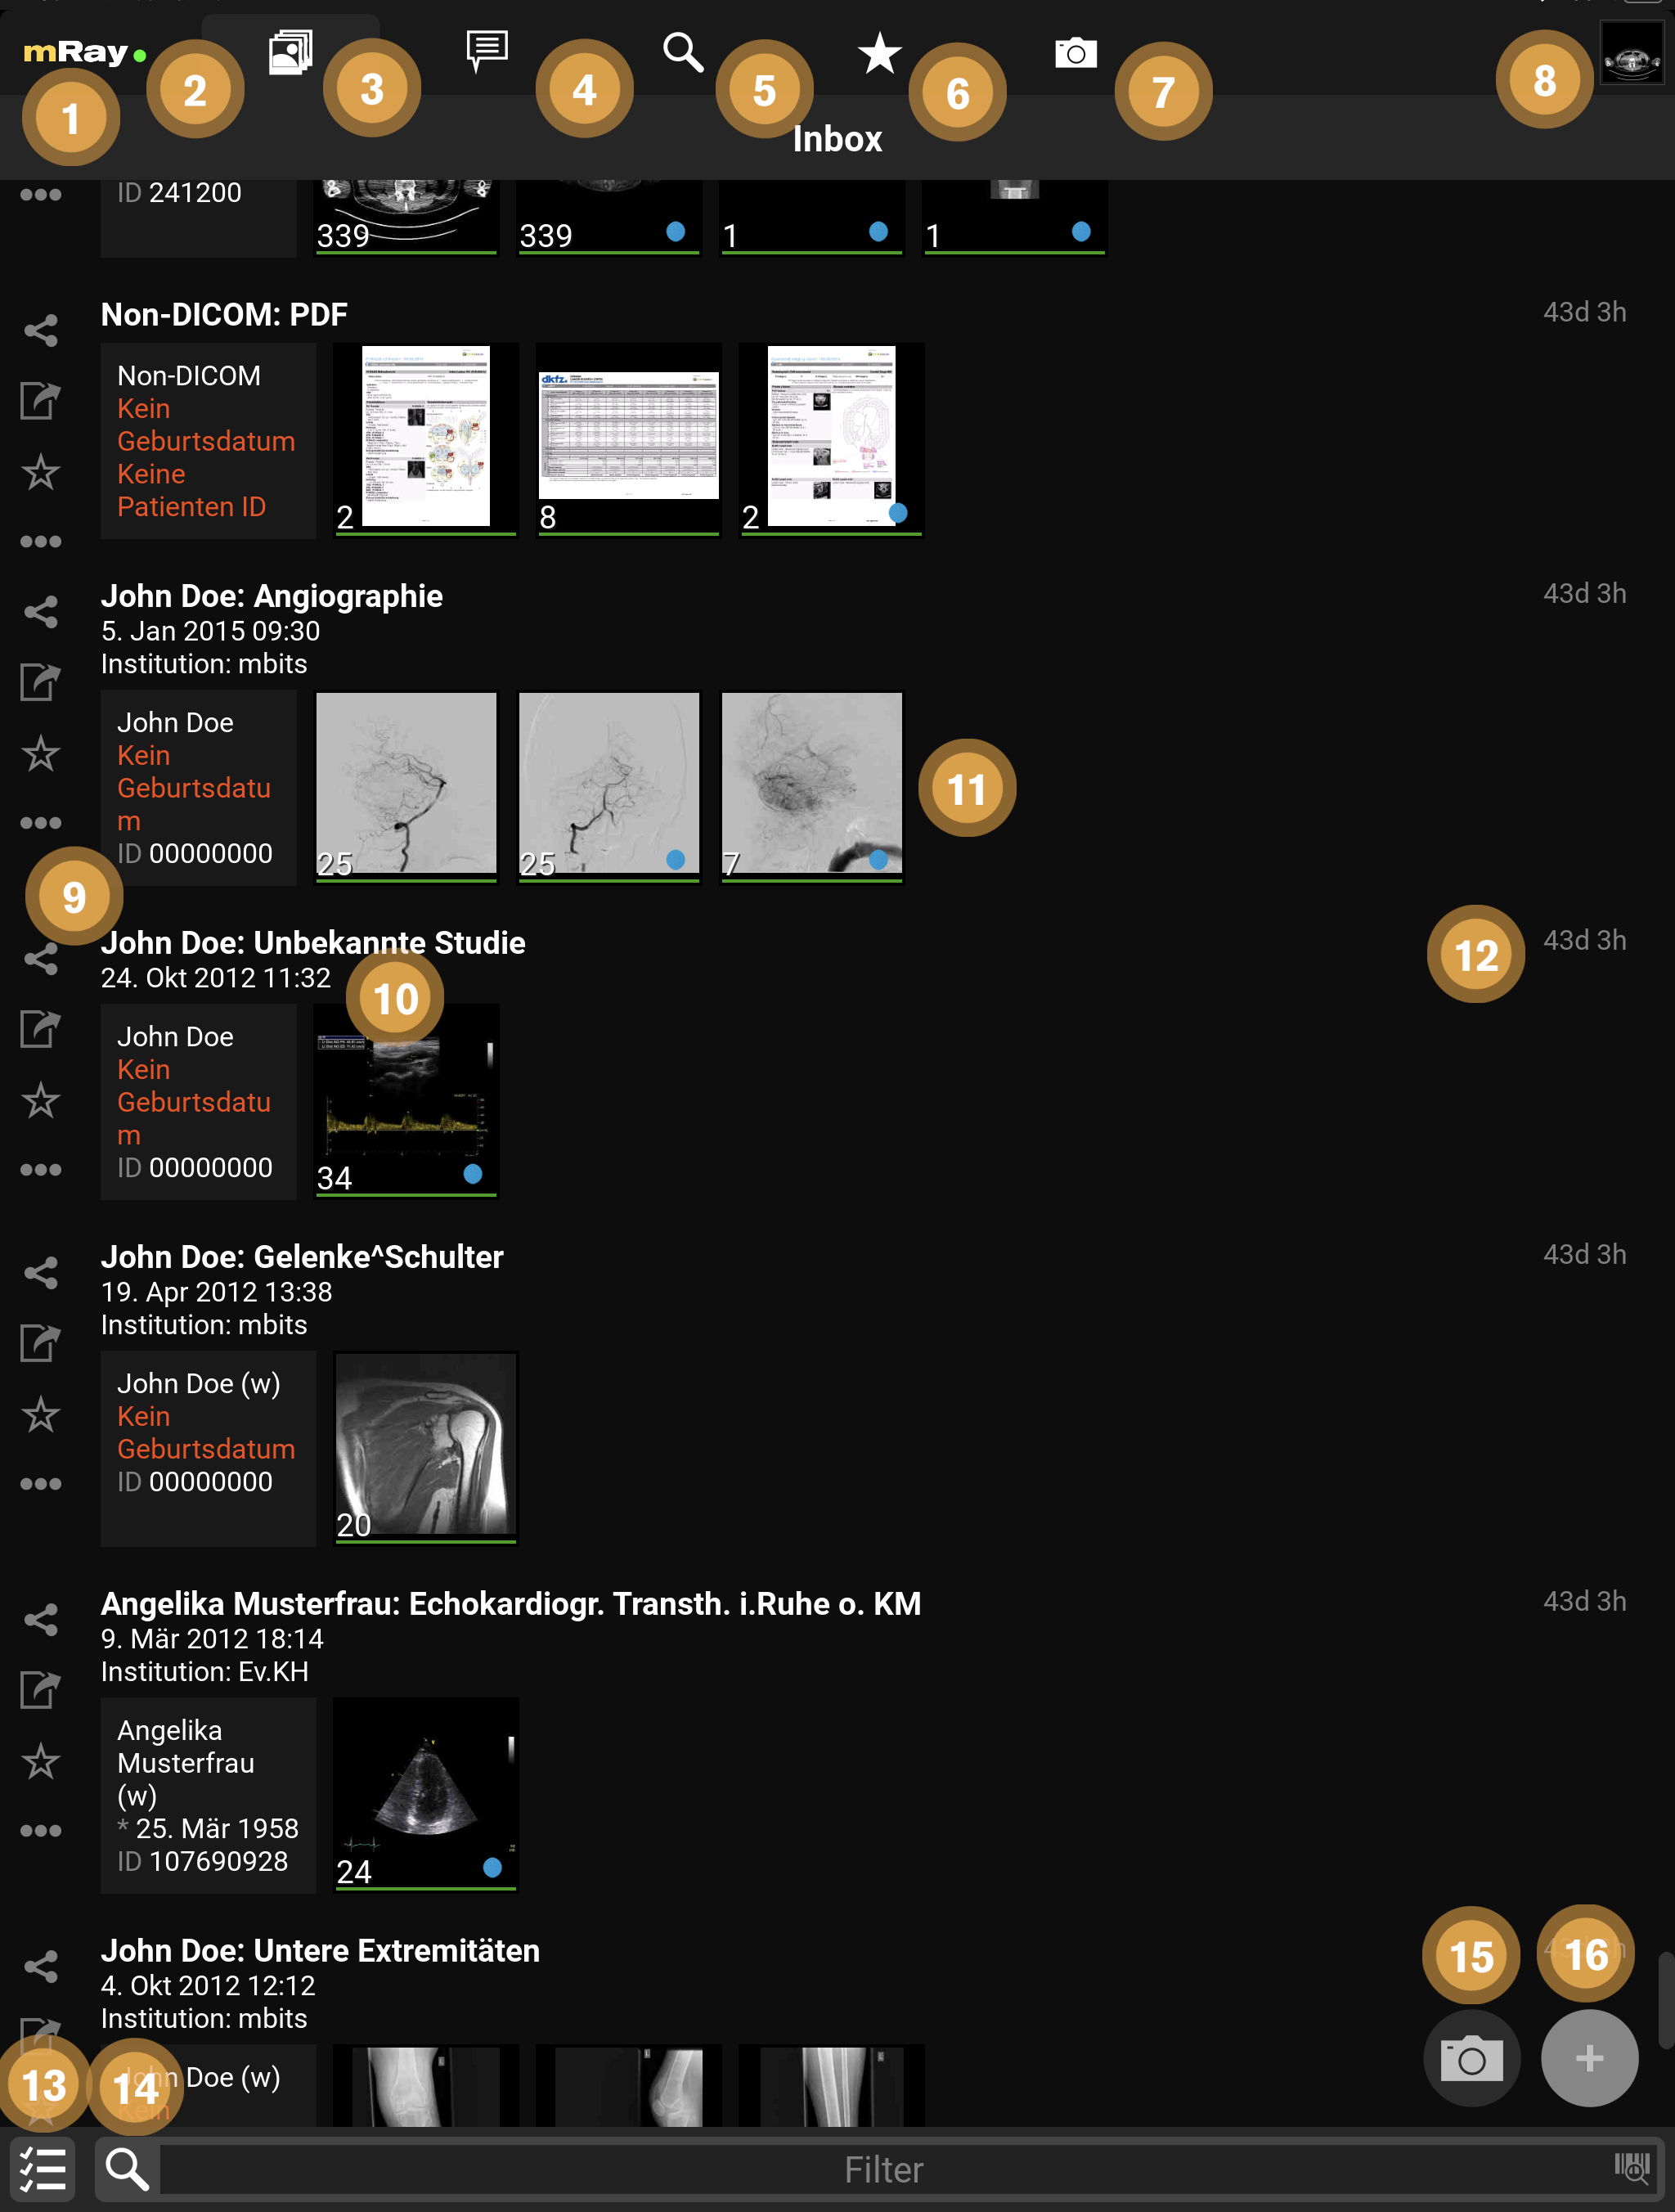

9.1. Inbox

The (Inbox) will be opened after logging in. With this you can browse and select the wanted DICOM files, which are enabled for you through the server. Thus you can see all files on the mRay server on which you have access rights.

|

Scrolling through long lists

Swipe up/down to scroll through lists or use the scrollbar on the right of a list to navigate quickly through them. |

-

By clicking the mRay logo you can open the main menu (see Main menu).

-

A green dot shows, if you are connected to the server. In case of a red dot you can work with the local saved files, but of course you can’t receive new files.

-

Switch to the Inbox or return to the beginning of the list if it is the active tab.

-

Switch to the Messaging menu (only if this function has been activated in your system).

-

Switch to the Search dialog. Here you can search the whole mRay database or query a PACS (if configured).

-

Switch to Favorites: It is possible to mark your favorites with the star symbol (Item 9). Favorites are working as a kind of bookmark and they will be deleted last by the automatically storage management of the application (which means your favorites will only be deleted if it is necessary due to your Settings to the data retention or due to low space on your device).

-

Switch to the Photo documentation

-

Click here to return to the viewer with the previously opened images.

-

Here you are able to quickly and easily share

, mark as favorite

, mark as favorite  or export

or export  a whole study.

Further actions on the whole study can be performed with the Context menu

a whole study.

Further actions on the whole study can be performed with the Context menu  .

. -

Shows information or rather missing information and meta data from a patient.

-

Shows an overview of the contained series in a study. By clicking a study you will get to the series selection (see Series selection). The green marker under any thumbnail indicates that the image data is stored locally and offline available.

-

The time will appear as soon as the data arrived in the mRay (by sending from a PACS and searching in the mRay database). mRay can be configured to automatically delete data after 'X' hours (default: after 8 hours).

-

Here enables selecting multiple studies for sharing.

-

Here you can filter your inbox by text entry. Please note: By filtering you don’t start a PACS query! See item 3 Search for PACS queries. Please also mind the notes to special characters in the 'known issues'.*

-

Take a photo: see Photo documentation section for further explanations

-

File-Upload: Upload your own DICOM data to the server. Only available if the server supports it.